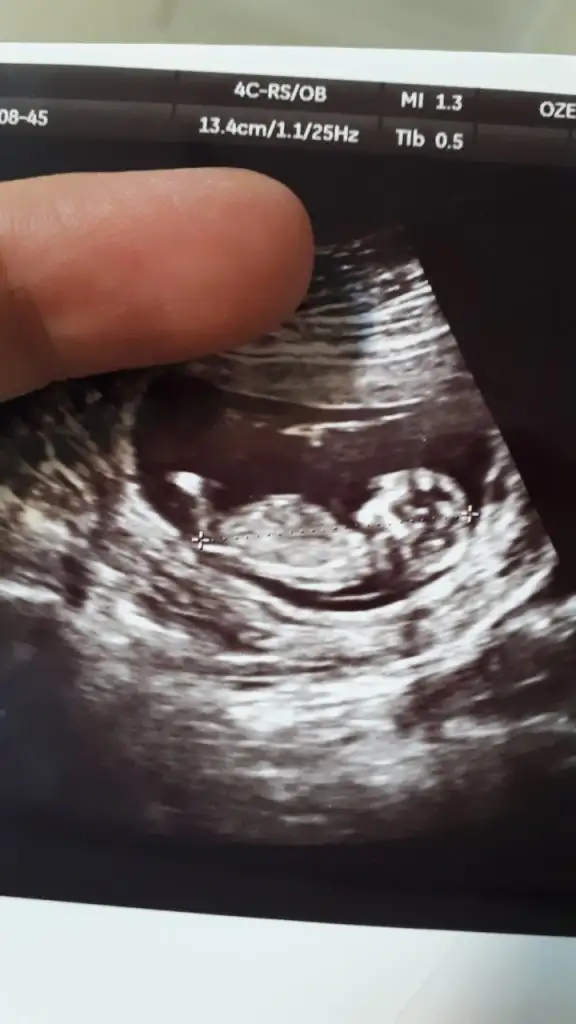

Bir de bana bakın hanımlar 11 haftalık nedir sizce Havalianne__ Havalianne__

• image.webp

image.webp

20,2 KB · Görüntüleme: 61

Yorum yapabilir misiniz